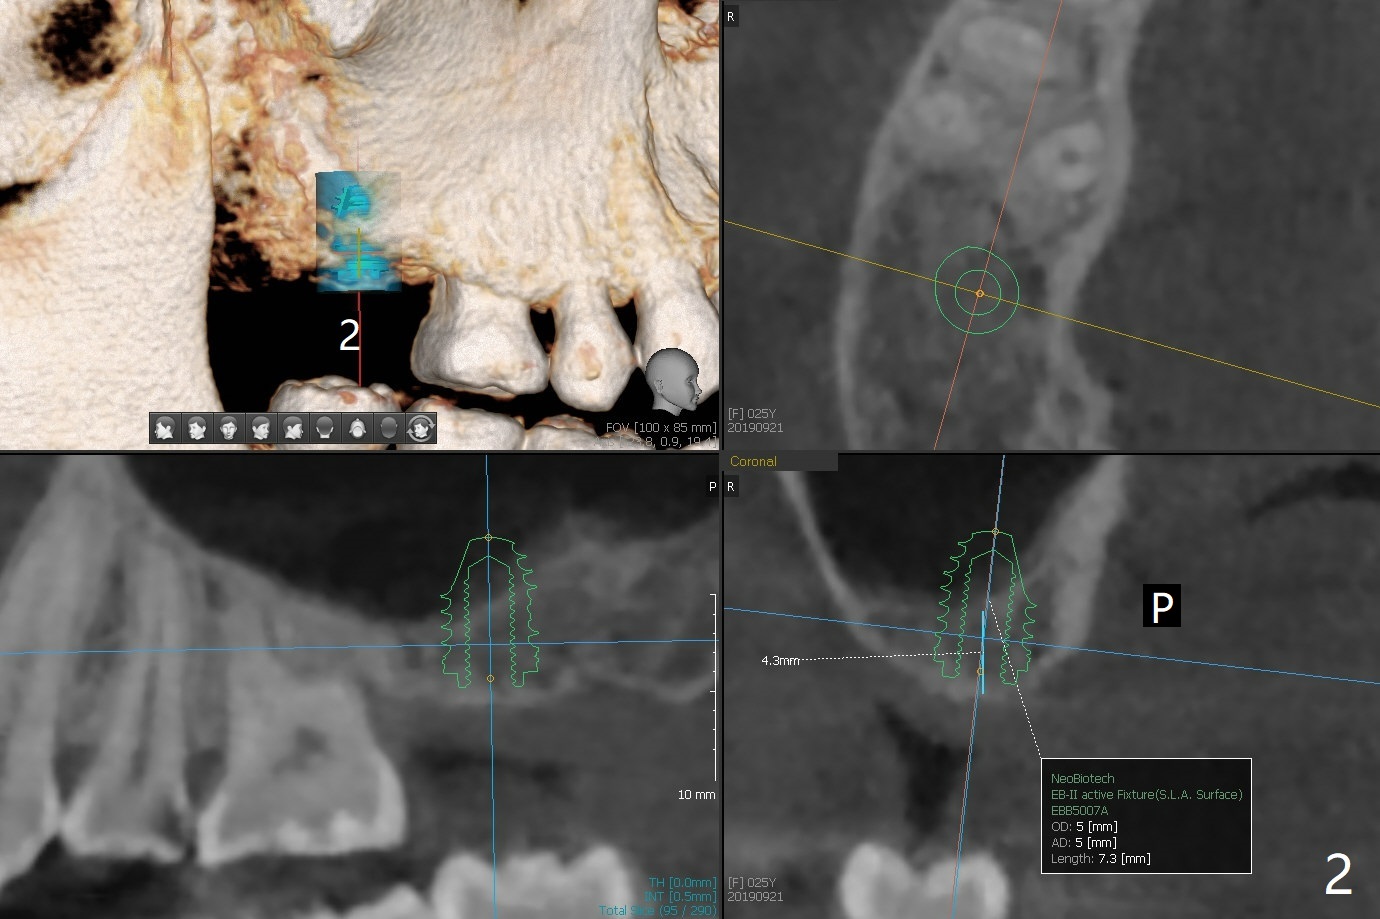

A 25-year-old woman had #2 and 18 extracted ~ 1 year ago (Fig.1). Because of the short and loose bone at #2, a short implant will be placed with sinus lift (PRF, Fig.2). If needed, probe mesiobuccal aspect of the osteotomy when it is close to the sinus floor to detect early sinus floor perforation before water lifting. It would be safer to use water lifting after the 1st sinus safe drill is used. Then water lifting and the 2nd sinus safe drill, et al. To reduce micromovement, a healing screw will be most likely placed instead of a healing abutment. In contrast, a healing abutment is possible at #18 (Fig.3).

Return to Upper Lower Molar Immediate Implant, Trajectory II Xin Wei, DDS, PhD, MS 1st edition 09/21/2019, last revision 02/02/2020